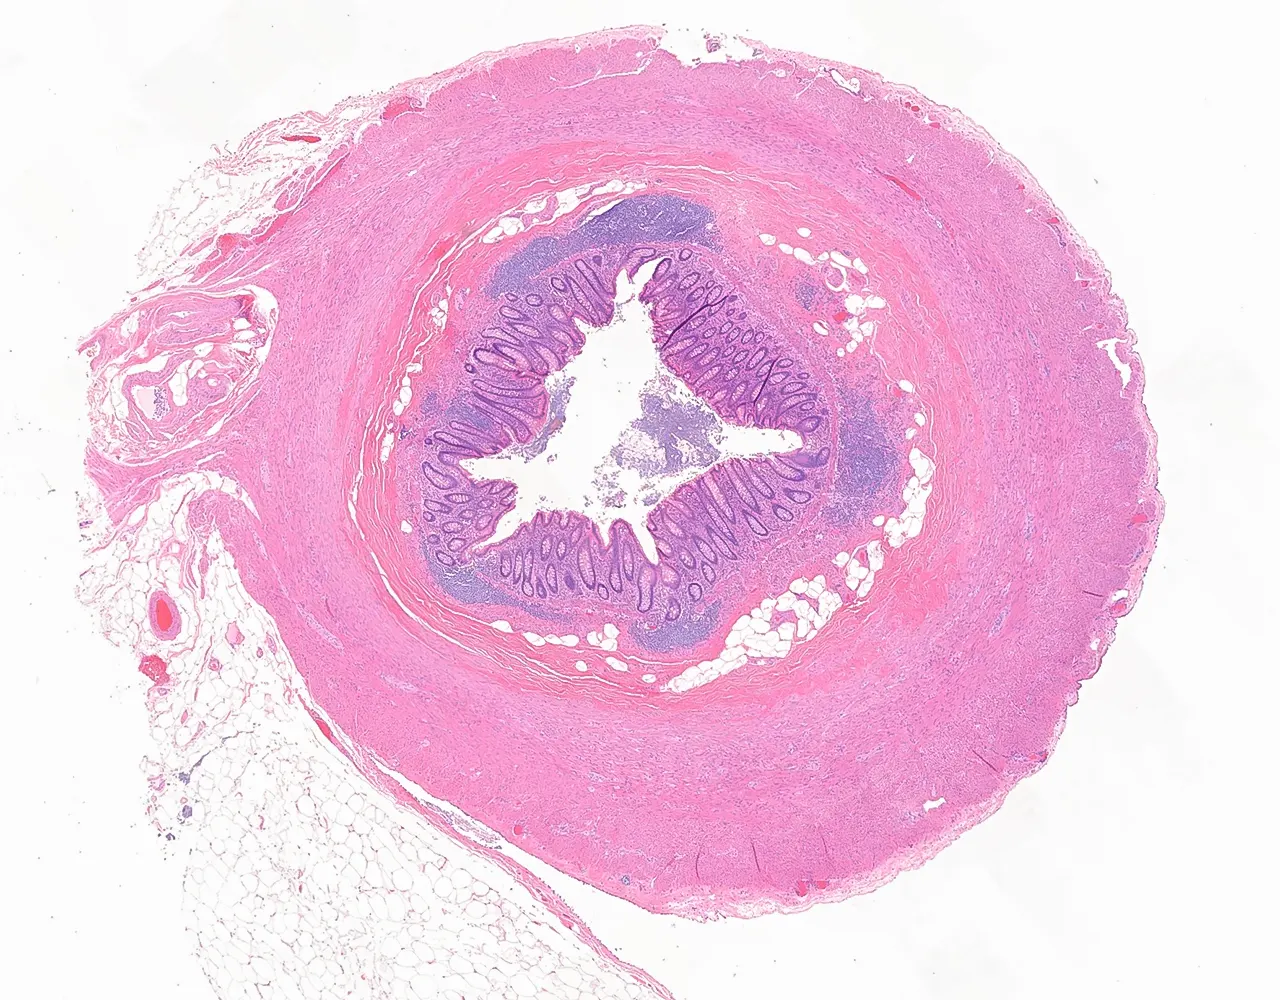

- Le gros intestin comprend le caecum, le côlon, le rectum et le canal anal.

- Le côlon ascendant et le côlon descendant sont majoritairement rétropéritonéaux, alors que le côlon transverse et le côlon sigmoïde sont intrapéritonéaux et recouverts par la séreuse.

- Le rectum est partiellement recouvert par une séreuse dans sa portion proximale, le reste du rectum est entouré par une adventice.